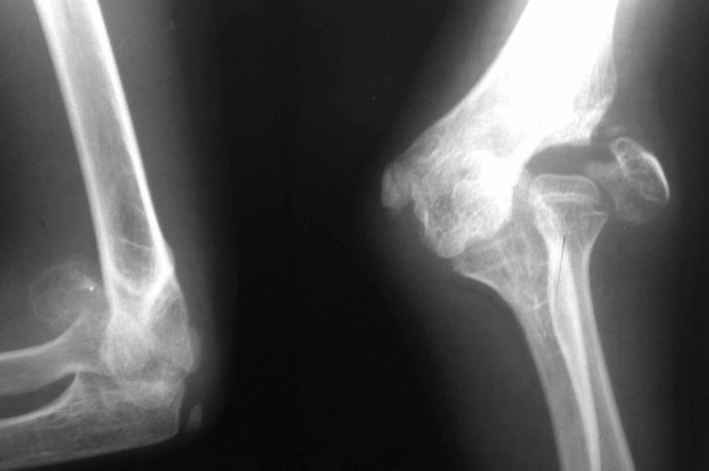

ПЕРЕЛОМ ЯКОЇ КІСТКИ І ЯКОЇ ЇЇ ЧАСТИНИ ВИ БАЧИТЕ НА РИСУНКУ?

варіанти відповідей

ДИСТАЛЬНОГО ДІАФІЗА

HUMERUS

ULNA

RADIUS

ПРОКСИМАЛЬНОГО ЕПІФІЗА

ДИСТАЛЬНОГО ЕПІФІЗА

ДІАФІЗА

МЕТАФІЗА

РОЗПІЗНАЙТЕ КІСТКУ. ПЕРЕЛОМ ЯКОЇ ЇЇ ЧАСТИНИ ВИ БАЧИТЕ НА РЕНТГЕНОГРАМІ?

FEMUR, ШИЙКА

ЛІКТЬОВОГО ВІДРОСТКА

ПРОМЕНЕВОГО ВІДРОСТКА